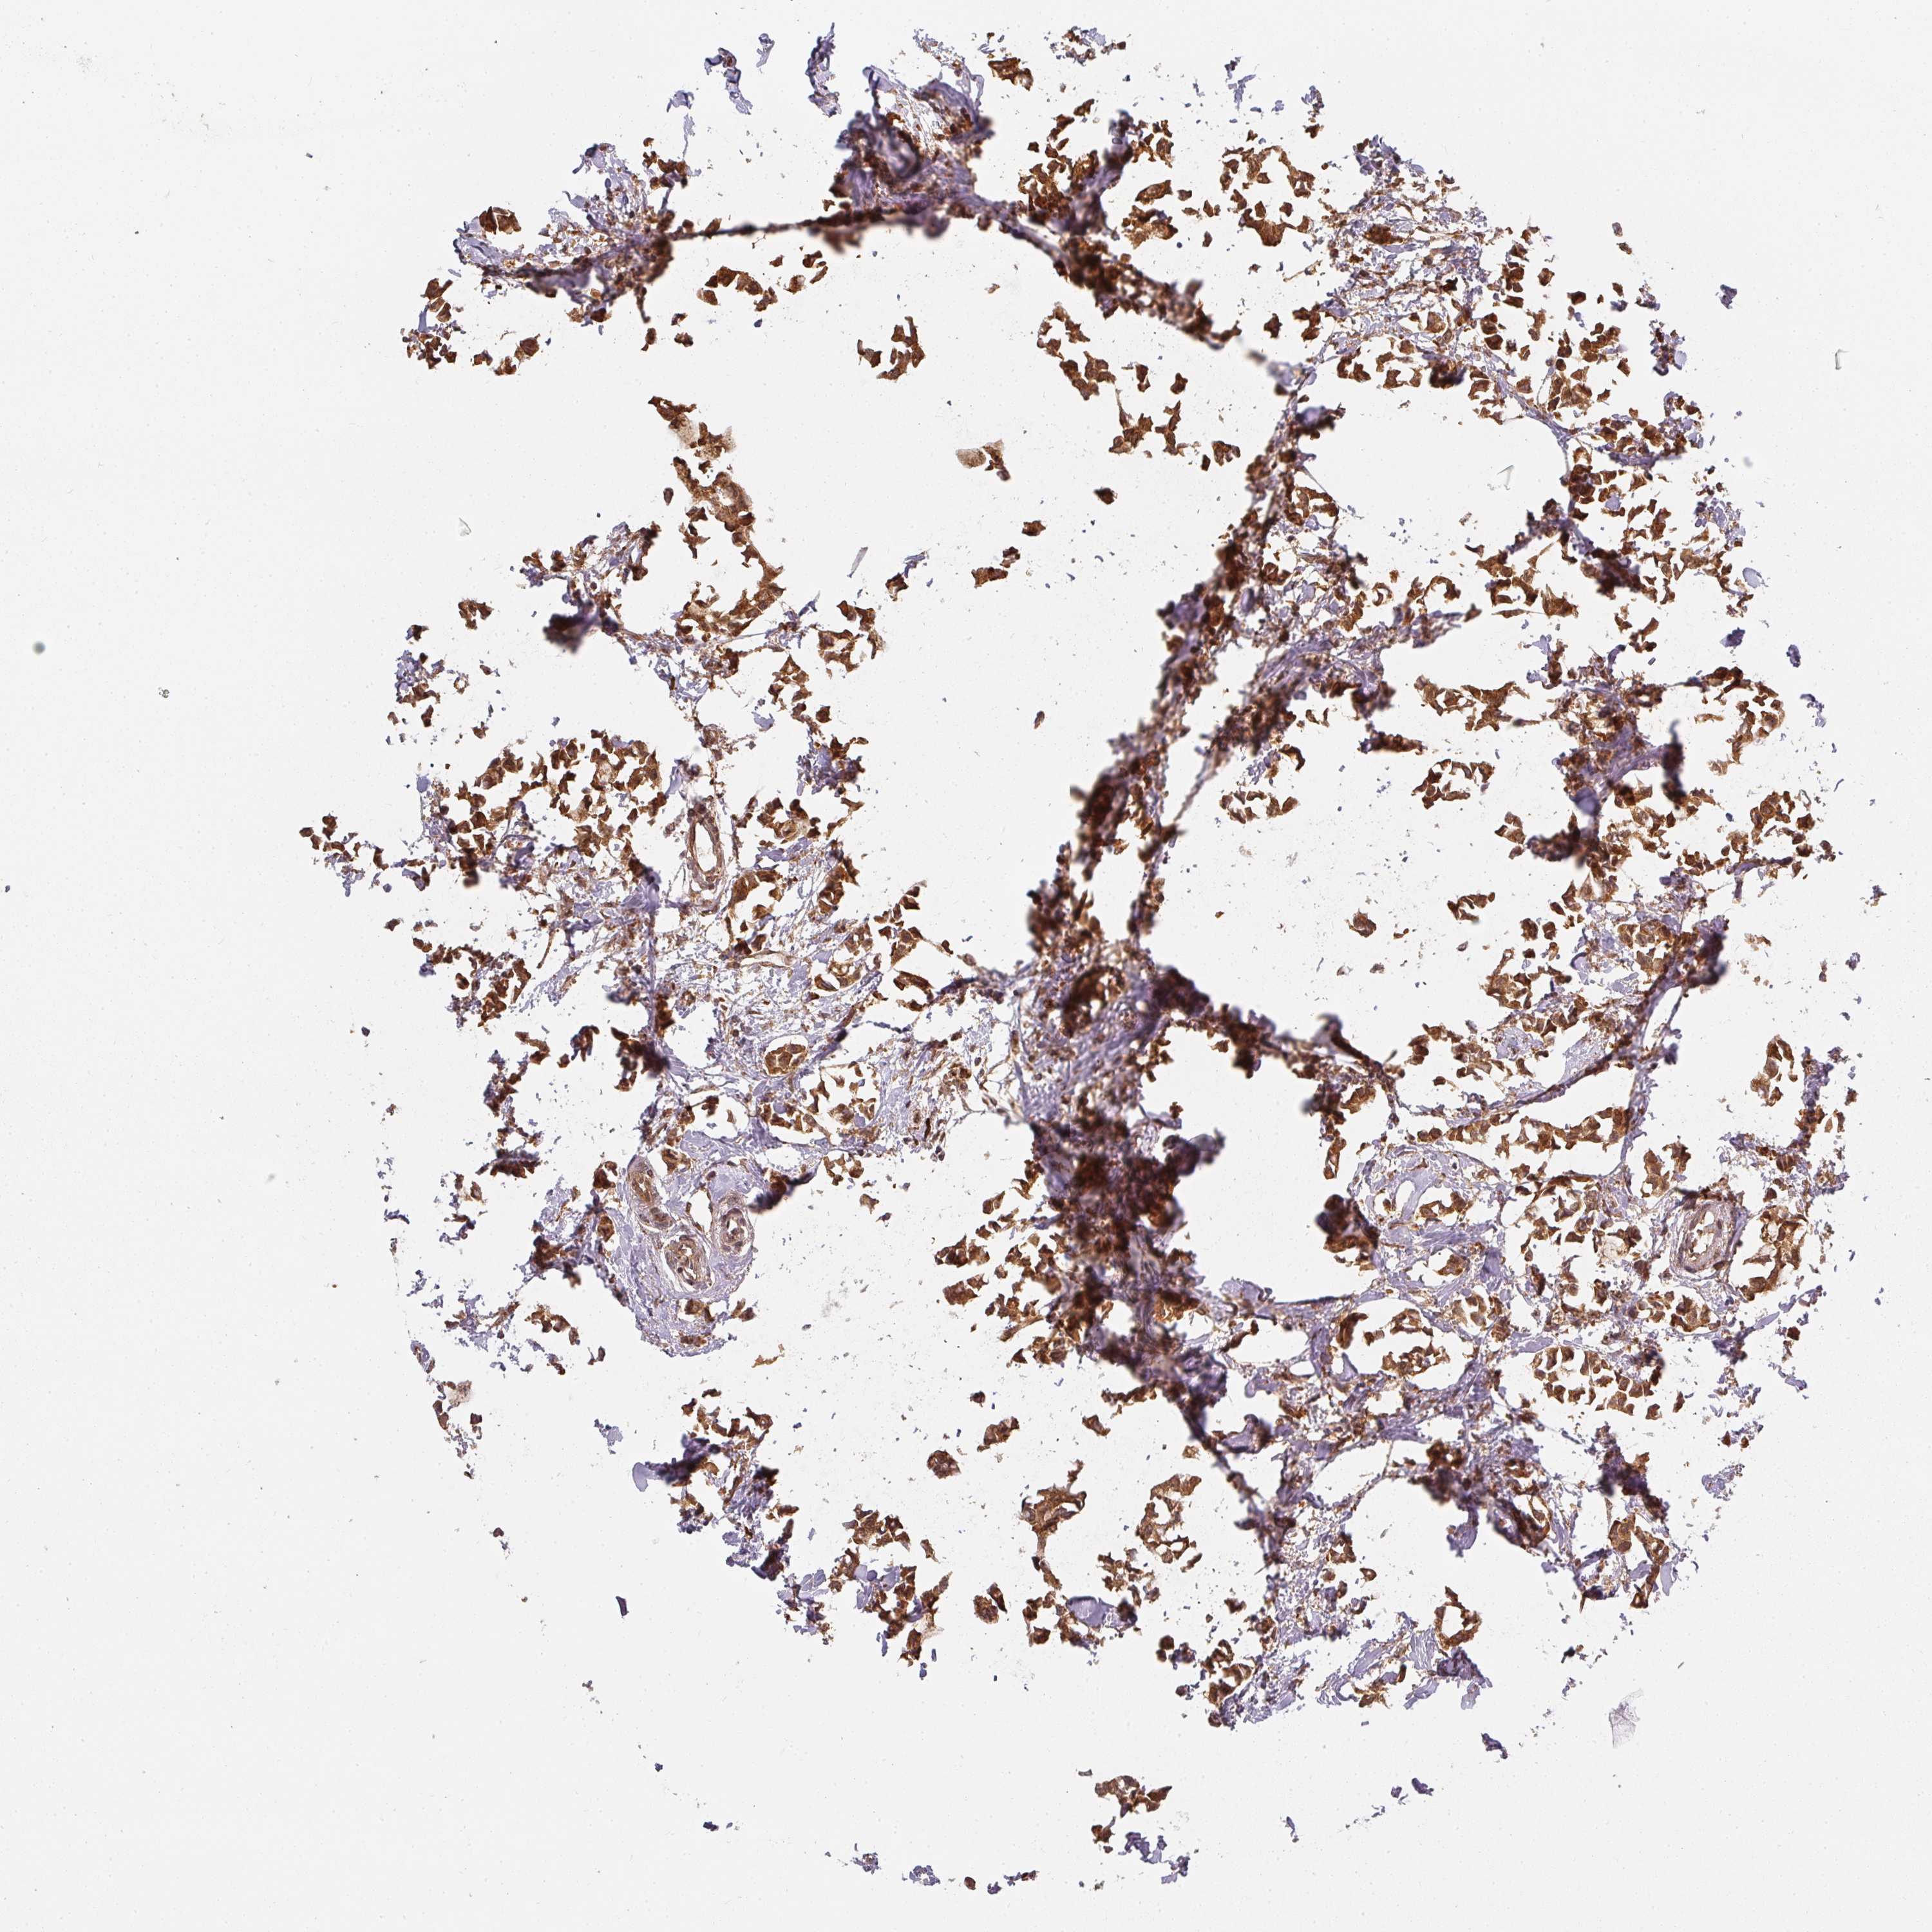

CANCER BREAST CANCER Show tissue menu

BRCA TCGA BRCA VALIDATION PROTEIN EXPRESSION